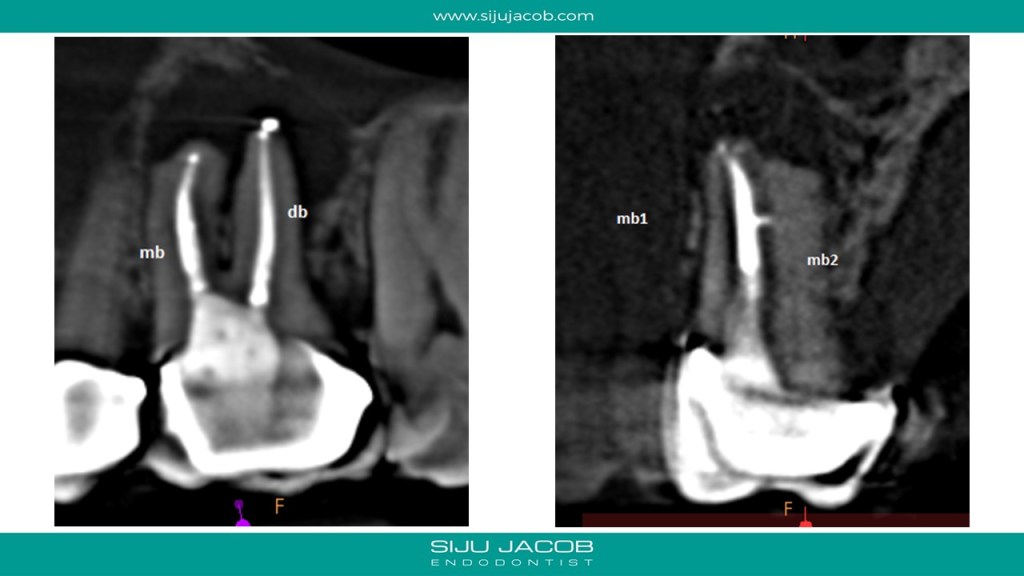

This is a Maxillary first molar treated several years ago and the patient came back with pain. CBCT shows missed MB2 with separate portal of exit. I located and treated only the MB2. Left the rest of the canals as they were.